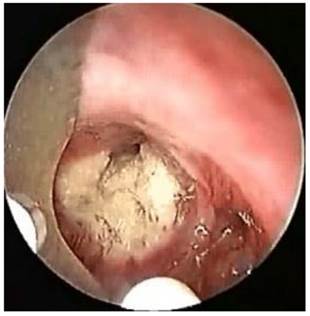

Figure 3

Argon Plasma Coagulation.

J Cancer Image